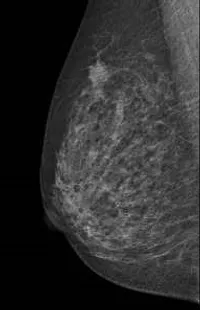

マンモグラフィー画像